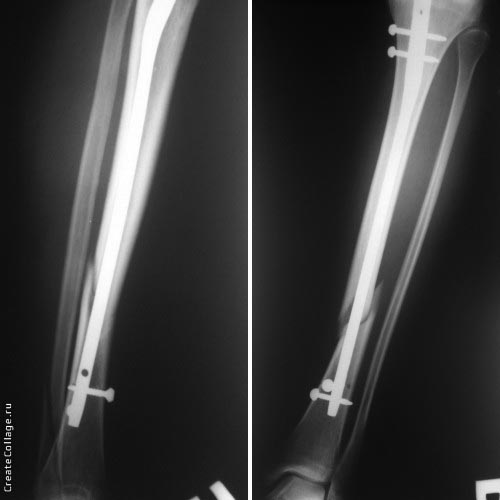

Пациент 26 лет, перелом б/берцовой кости в н/з, при поступлении наложено

скелетное вытяжение, спустя 14 дней с момента поступления выполнена

операция БИОС. Выписана. После консультации пациентки только по

Ro-граммам в другой больнице получен ответ "накосячили". Уважаемые

коллеги, а какая ваша будет оценка? Согласен что гвоздь коротковат.